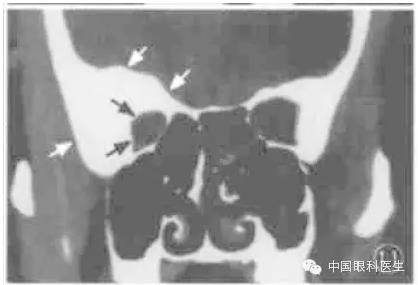

2.恶性肿瘤

恶性肿瘤呈浸润性增长,CT扫描常显示肿瘤边界不清楚,形状不规则,常合并骨破坏,如副鼻窦癌眶内侵犯(图8)。但有些眶内恶性肿瘤显示类似良性肿瘤的CT征,如形状类圆形、边界清楚、内密度均质、无明显骨破坏等,如横纹肌肉瘤、淋巴瘤、泪腺腺样囊性癌等。

图8 左筛窦恶性肿瘤内侵犯冠状CT显示左筛窦密度增高,筛骨纸板破坏(箭头),眶内侧较大高密度占位病变,形状不规则,眶腔扩大

5.骨增生

骨增生即骨肥厚。能引起眶骨增生的病变主要包括蝶骨嵴脑膜瘤和骨纤维异常增生症。前者CT显示蝶骨嵴(眶外壁)肥厚,邻近的眶内或颅内有软组织块影;后者为广泛骨增生,常累及额骨、眶外壁、筛骨、眶顶、上颌骨等,病变边界不清楚,眶内或颅内无软组织块影,由于眶壁增生致眶腔缩小(图10)。

钙化在眶内肿瘤中虽不多见,但具有特征性诊断意义。钙化分两种:一种为血管内钙化,因其呈圆形,也称静脉石(图11),主要见于静脉血管瘤,静脉曲张,少见于海绵状血管瘤等病变;另一种是不规则钙化,见于脑膜瘤、泪腺上皮性恶性肿瘤、神经鞘瘤等。

图11右侧骨纤维异常增生症CT显示右眶顶、外侧壁广发骨增生(白箭头),眶腔缩小(黑箭头)